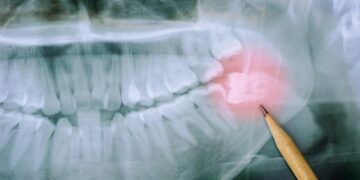

Lire plusVotre dentiste vous a dit que vos dents de sagesse étaient sur le point de sortir et qu’il fallait les...